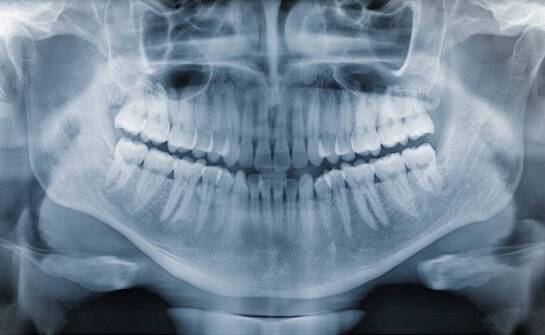

RTG zębów – co może wykryć i dlaczego dentysta tak często je zleca?

RTG z ębów to kluczowe narzędzie diagnostyczne w stomatologii, umożliwiające dokładne zbadanie stanu zdrowia jamy ustnej. Dzięki temu badaniu dentysta może wykryć problemy niewidoczne gołym okiem, takie jak próchnica czy choroby przyzębia. Istotność RTG w codziennej praktyce stomatologicznej jest nie